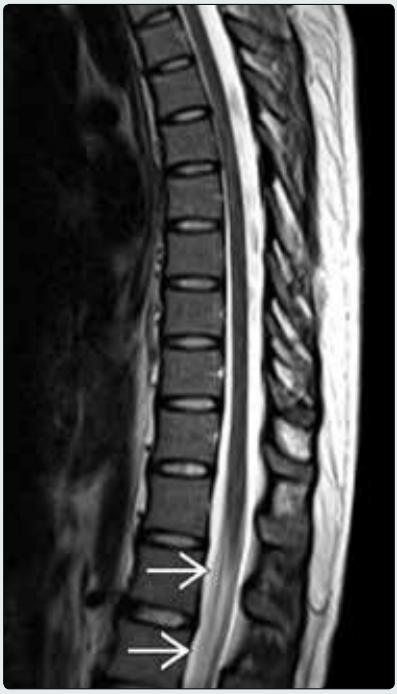

GBS患者,MR矢状位平扫T2WI图像显示马尾增厚→,圆锥形态和信号正常,抗神经节苷脂抗体滴度升高证实为GBS